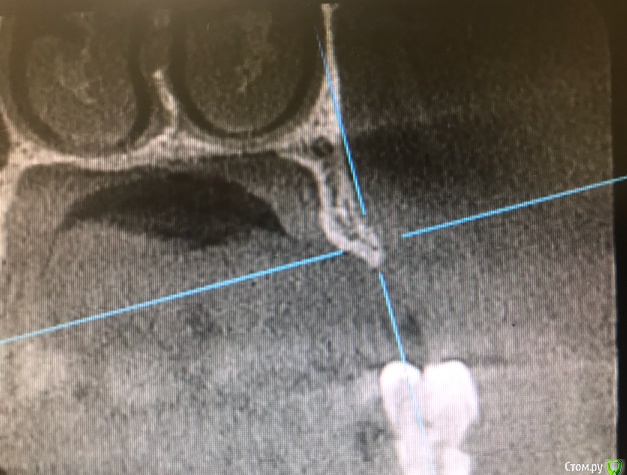

колесников Опубликовано 15 марта, 2019 Автор Поделиться Опубликовано 15 марта, 2019 Вот так выглядит интегрированый графт и соответственно не созревший. Время ожидания примерно равнозначное Ссылка на комментарий

колесников Опубликовано 16 марта, 2019 Автор Поделиться Опубликовано 16 марта, 2019 (изменено) Ну как бы тут все очевидно. Слева стала костью,справа нет. Но должен вам отметить,что даже в случае неудачи (как кажется)потери нет. Задача стояла не увеличить объём для имплантации или укрыть Имплант,а снять напряжение с вершины гребня и дать созреть десне. Имплант в нативной кости,он интегрирован,десна успела созреть за это время,возможно будет не так объёмно как хотелось бы,но у меня в запасе этап раскрытия ,фдм зарос ,есть с чем поработать. Все что не интегрировалось ,лизируется самостоятельно,выскребать ничего не нужно,ещё подождать. Изменено 16 марта, 2019 пользователем колесников Ссылка на комментарий